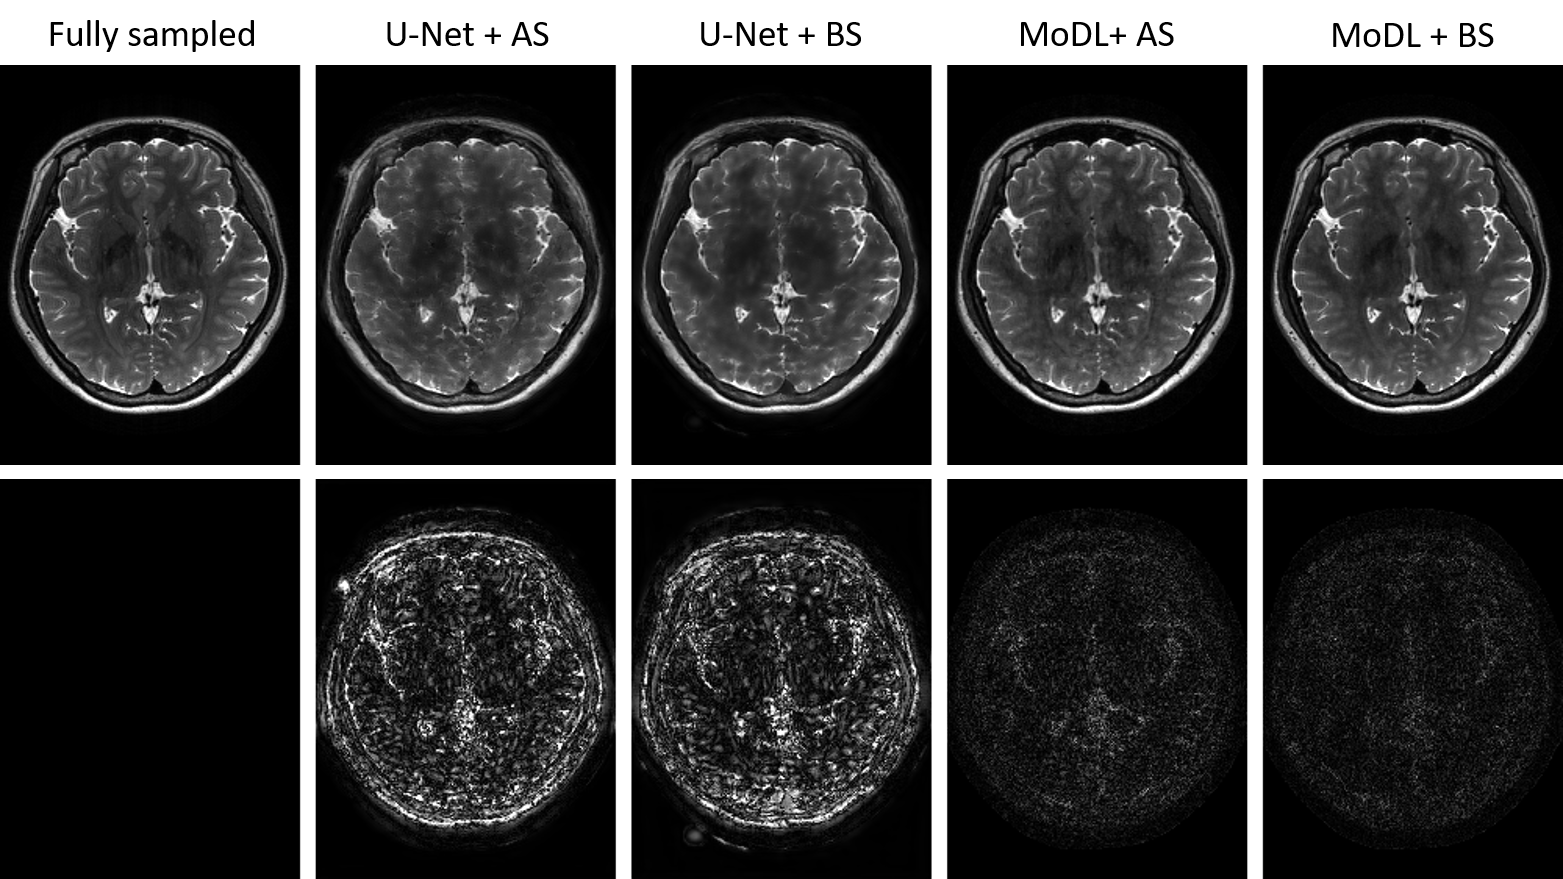

Figure 2: Reconstruction results on one test slice by four combinations of reconstruction network and sampling pattern optimization network with 10% under-sampling ratio. First row: reconstruction results; second row: 5×5\times absolute error maps (window level: [0, 0.5]). MoDL + BS equipped with ST estimator had the best performance.

3.2 Comparison with LOUPE

Fig. 2 shows the reconstruction results from one of the test subjects to demonstrate the performance improvement of the extended LOUPE over vanilla LOUPE. Four combinations of reconstruction network and sampling pattern optimization network were tested and compared. Binary sampling patterns were generated during test phase. From Fig. 2, MoDL provided better reconstruction results compared to U-Net, while for both U-Net and MoDL reconstruction networks, BS (binary sampling) gave less noisy reconstructions than AS (approximate sampling) during test phase. Quantitative comparisons in terms of PSNR (peak signal-to-noise ratio) and SSIM (structural similarity index measure [29]) are shown in Table 1, where MoDL + BS had the best performance.